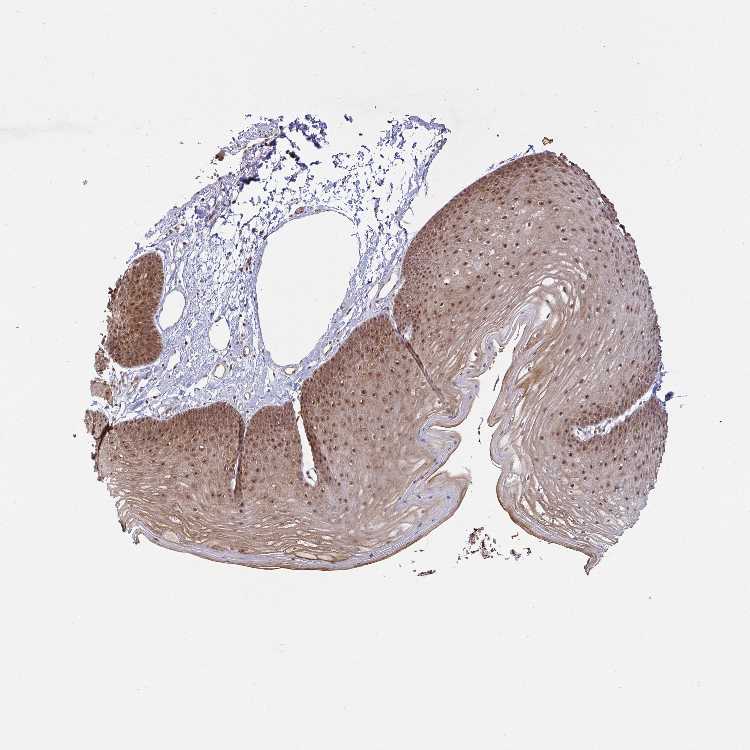

SKIN 1 - Antibody stainingi

Antibody staining in the annotated cell types in the current human tissue is reported as not detected, low, medium, or high, based on conventional immunohistochemistry profiling in selected tissues. This score is based on the combination of the staining intensity and fraction of stained cells.

Each image is clickable and will lead to virtual microscopy that enables deeper exploration of all samples and also displays staining intensity scores, fraction scores and subcellular localization as well as patient and tissue information for each sample.

Antibody HPA060459

Langerhans Medium

Fibroblasts Medium

Keratinocytes Medium

Melanocytes Low